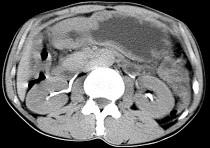

问题 男,56岁,无规律上腹痛,左锁骨上淋巴结肿大,消瘦、乏力,影像检查如图,最可能的诊断是 ( )

选项 A.腹膜结核 B.胃溃疡穿孔 C.胃癌并盆腔种植 D.胃及腹腔淋巴瘤 E.肠系膜淋巴管瘤

答案 C